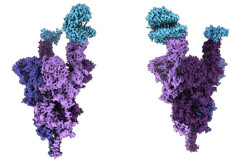

La OMS sigue considerando la viruela del mono como emergencia de salud pública de preocupación internacional

El Comité de Emergencia del Reglamento Sanitario Internacional (RSI) ha decidido continuar considerando la viruela del mono como una emergencia de salud pública de preocupación internacional (PHEIC, por sus siglas en inglés), según ha informado el director general de la Organización Mundial de la Salud (OMS), Tedros Adhanom Ghebreyesus.